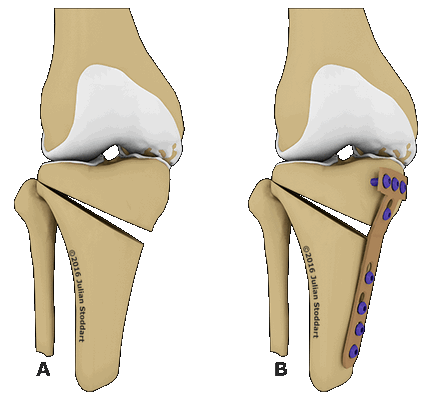

Схематичное изображение проведения операции.

Корригирующая остеотомия коленного сустава — операция, устраняющая врожденные и приобретенные костные деформации. Во время хирургического вмешательства врач иссекает заранее обозначенный участок костной ткани и соединяет свободные фрагменты костей имплантатами. В результате ось механической нагрузки переносится на здоровый участок сустава. Операция проводится под полной или спинальной анестезией. После лечения ортопед фиксирует нижнюю конечность пациента гипсовой повязкой на время восстановления. Проводится реабилитация.

Остеотомия с металлоконструкцией.

- Клиновидная закрытая. Разрез кожи производится в латеральной или передней области колена для доступа к верхнему эпифизу большеберцовой кости или нижнему эпифизу бедренной кости. После иссечения ткани свободные поверхности кости фиксируют металлическими пластинами или скобами.

- Клиновидная открытая. После разреза кожи в передней или боковой области колена проводится неполная остеотомия. Концевой отдел большеберцовой кости разъединяется на две части с формированием диастаза. Далее костные участки соединяют металлической пластиной и аутотрансплантатом из таза пациента.

Остеотомия коленного сустава: визуальное изображение процедуры.

Костная ткань удаляется с помощью остеотома. Для предотвращения повреждения сосудов и нервов, проходящих через коленный сустав, коррекция проводится под контролем флуороскопа или рентгеновского аппарата. После пластики кожный покров сшивается, и нижняя конечность фиксируется гипсовой повязкой или шиной.

Не существует единого метода оперативного вмешательства, подходящего при любых показаниях. При выборе хирургической техники врач учитывает запланированный угол коррекции. Методы визуализации помогают точнее восстанавливать ось нижней конечности. В современной ортопедии чаще всего проводится открытая клиновидная остеотомия большеберцовой кости выше уровня бугристости.